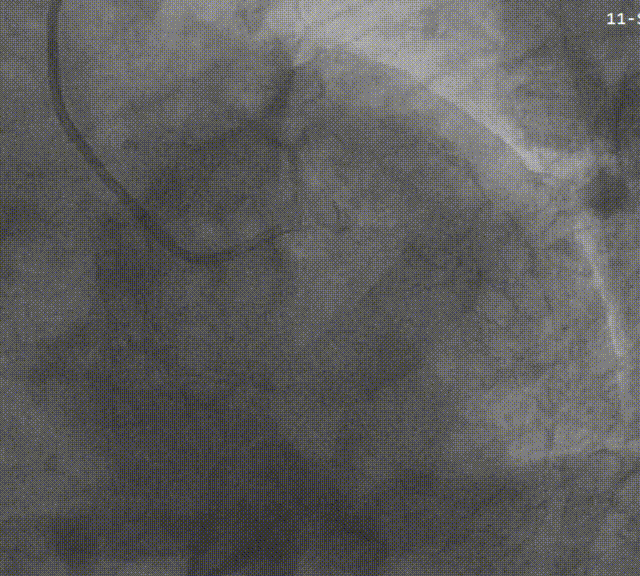

右冠造影提示原支架通畅,近段支架内内膜增生